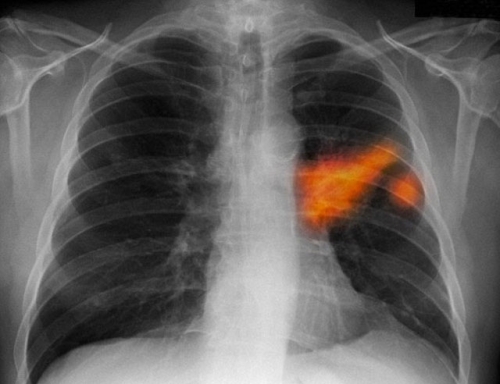

Old  Default Vợ bị mắc bệnh ung thư phổi chỉ vì thói quen hàng ngày của chồng

Câu chuyện về người phụ nữ đi khám phát hiện ra căn bệnh ung thư phổi được chia sẻ.Ngày nay,số người tử vong vì căn bệnh ung thư phổi ngày một nhiều mà nguyên nhân đều không phải do hút thuốc.Bác sĩ cho biết nguyên nhân chính dẫn đến bệnh ung thư phổi của phụ nữ từ thói quen hàng ngày của chồng.

Cách đây không lâu, một nữ bệnh nhân tên Nguyễn Thị Nh. ở Hưng Yên mắc ung thư phổi phải nhập viện K Trung ương để điều trị. Sau hơn 3 tháng phát hiện bệnh, bệnh nhân Nh. đang phải điều trị hóa chất để kìm hãm sự phát triển của tế bào ung thư. Tuy nhiên, do ảnh hưởng của chạy hóa chất, sức khỏe bệnh nhân bị giảm sút rất nhiều.

Điều đáng nói, khi bệnh nhân nhập viện, các bác sĩ chẩn đoán một trong những nguyên nhân dẫn đến căn bệnh ung thư phổi của bà Nh. do phải hút thuốc lá thụ động. Điều này khiến bản thẩn bà và gia đình vô cùng sửng sốt.

Theo chia sẻ của bà Nh. hàng ngày chồng và con trai bà hút thuốc vô cùng nhiều. Thậm chí, chồng bà hút mỗi ngày một bao. Chính vì thế, mùi khói thuốc đối với bà Nh. trở thành quen thuộc. Ban đầu, bà Nh. cũng góp ý về thói quen này của chồng con nhưng ai cũng bỏ ngoài tai. Họ dần coi đó là điều bình thường. Nhưng có ai ngờ, làn khói thuốc trong gia đình lâu nay âm thầm phá huỷ tế bào lành của phổi của bà Nh.

Theo bác sĩ Vũ Hải - bệnh viện K Trung ương, nhiều công trình nghiên cứu cho thấy, mối liên quan giữa bệnh ung thư phối với tác nhân thuốc lá. Đây là nguyên nhân hàng đầu gây ung thư phổi.